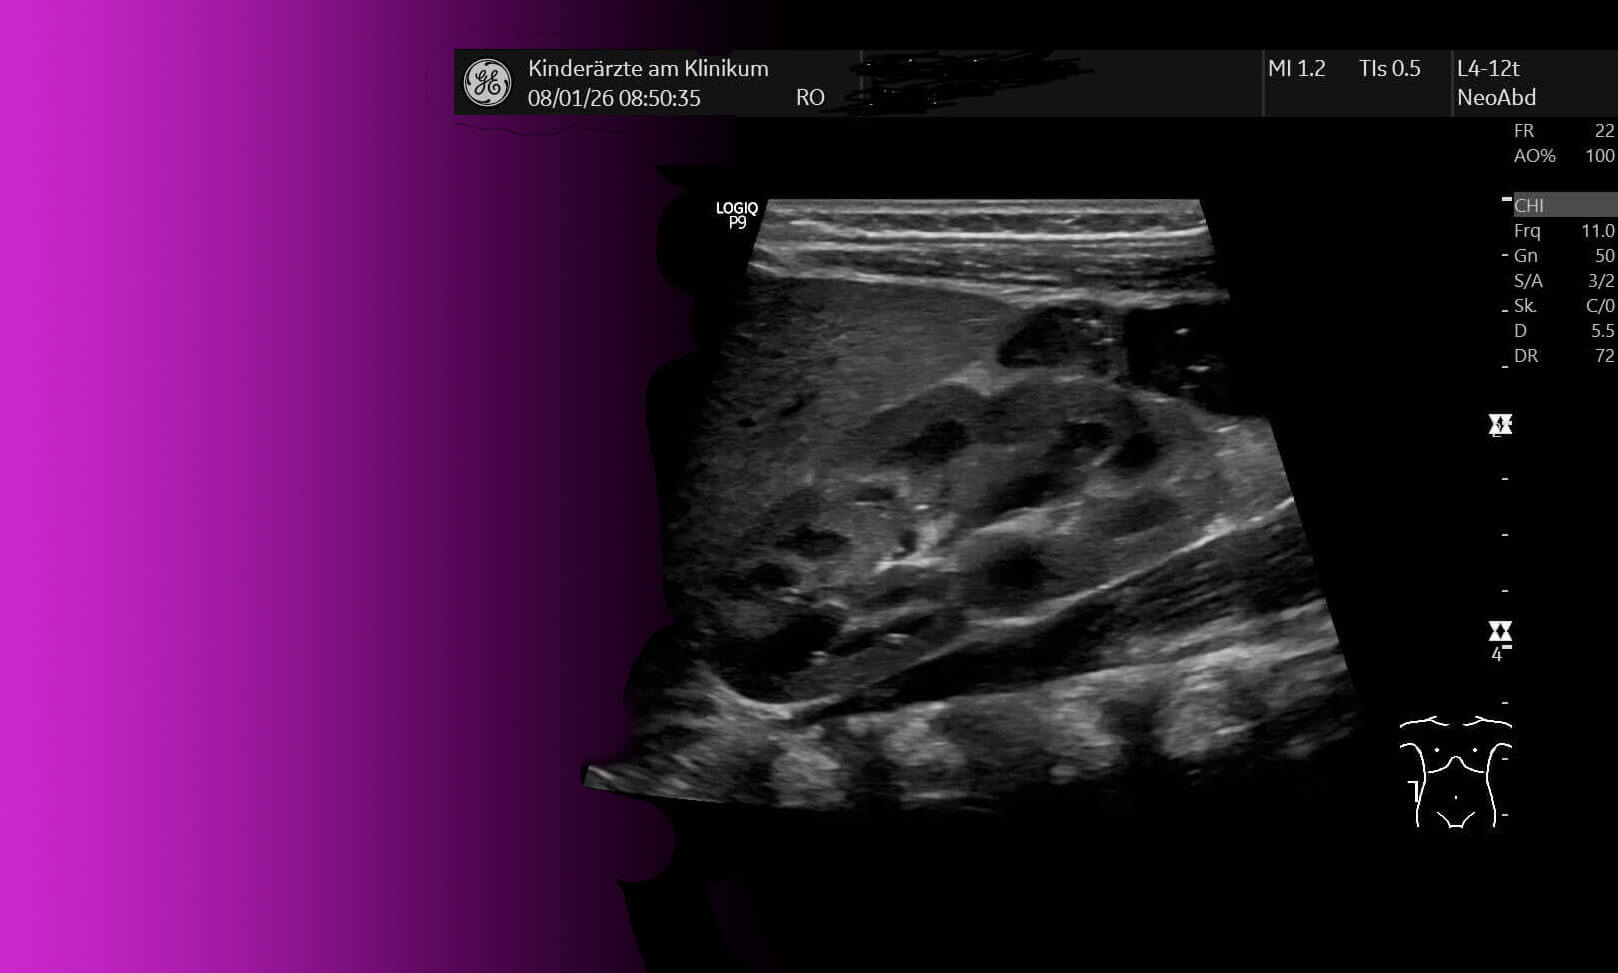

Neben der Sonographie von Nieren und ableitenden Harnwegen einschließlich Restharnprüfung, der Urindiagnostik einschl. Urinmikroskopie sowie auch Untersuchung des Sammelurins ist eine umfangreiche Labordiagnostik, die insbes. bei der Abklärung von Blut/Eiweiß im Urin notwendig ist, möglich.